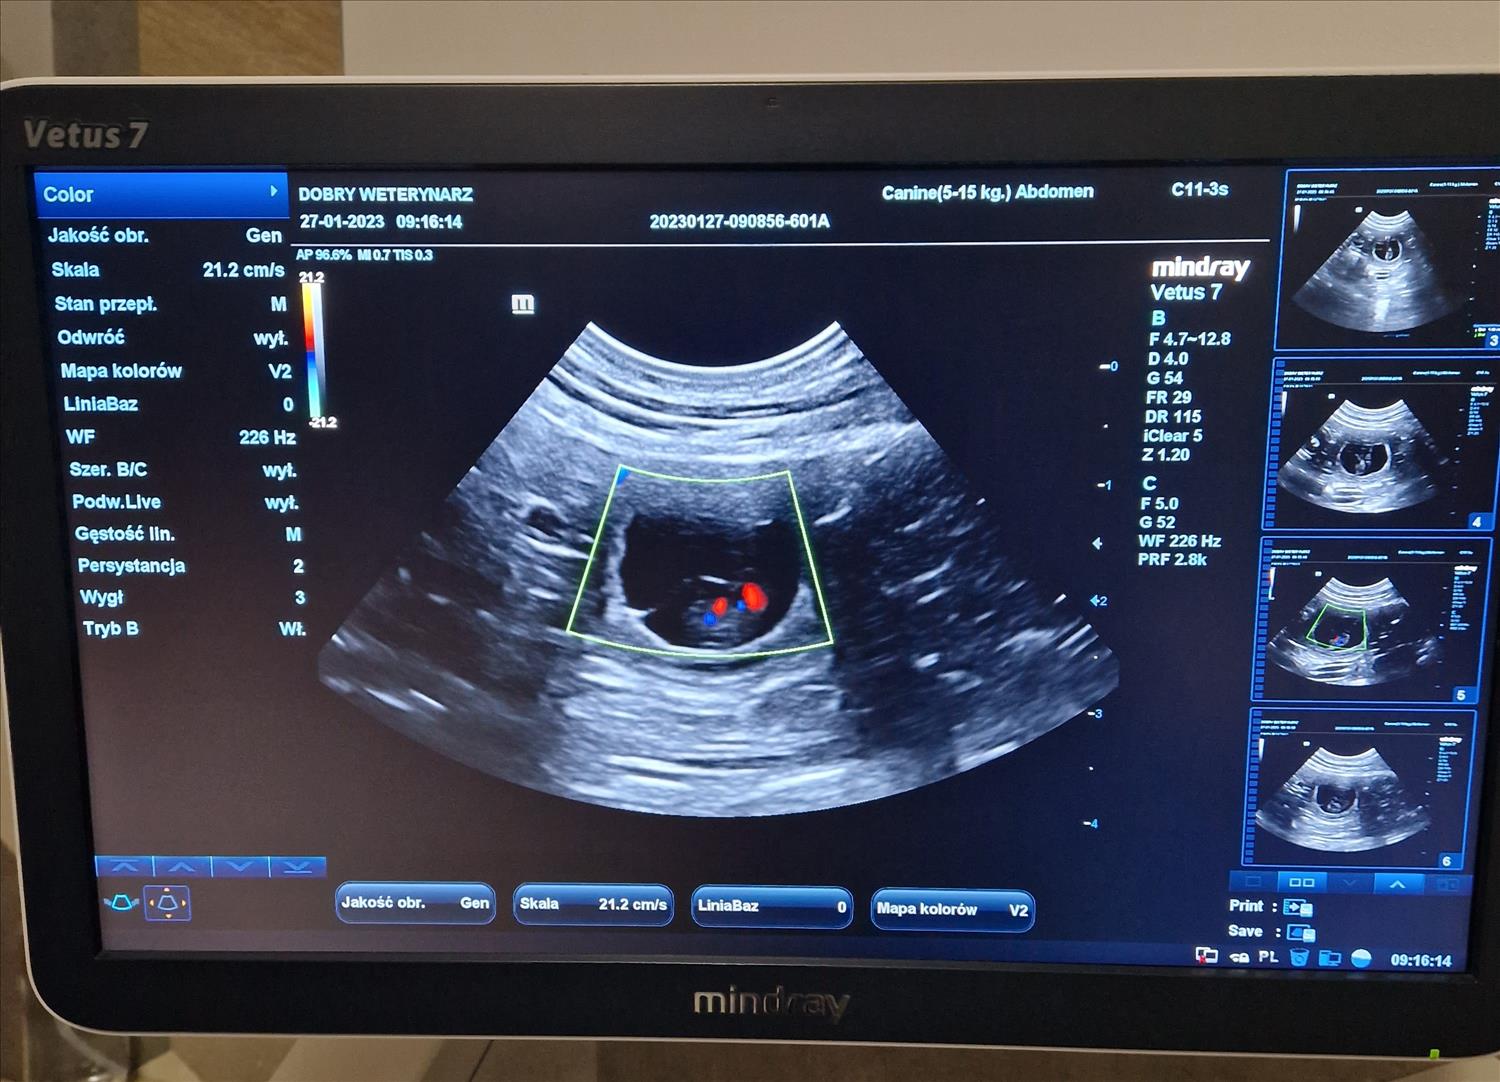

Z PAMIĘTNIKA HODOWCY: CIĄŻA CHILLI

Chilli's pregnancy diary

Ciąża u suni to najbardziej fascynujący okres dla hodowcy!